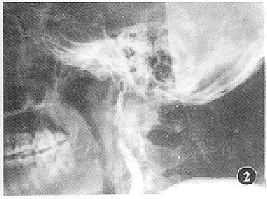

图1 左颈内动脉C4段,示一1 cm×1.5 cm囊袋状突起,并有造影剂外渗。诊断C4段外伤性动脉瘤破裂

图2 可脱性球囊栓塞未成功,采用不锈钢圈闭塞左颈内动脉